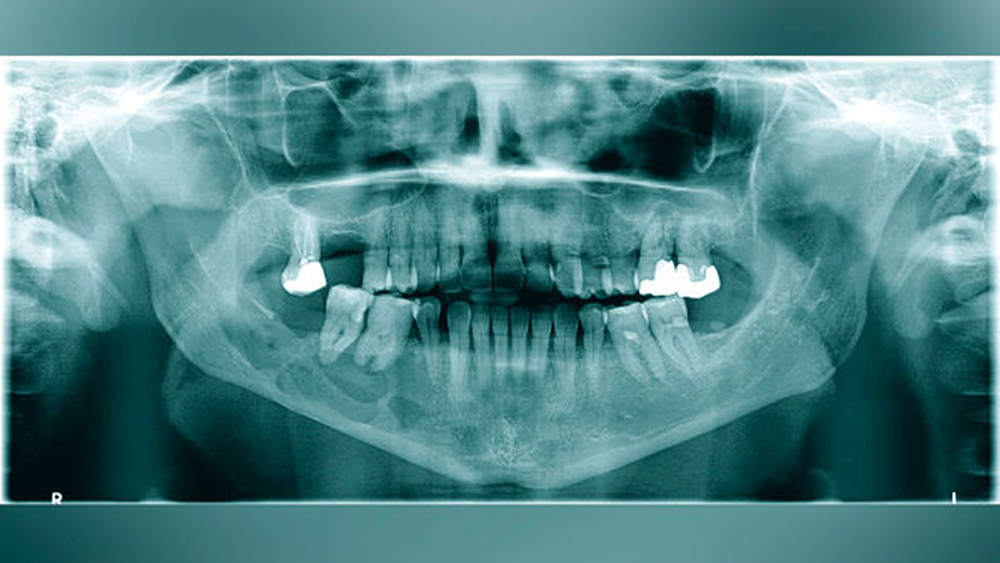

Eine 57-jährige Patientin stellte sich mit einer seit dem Vortag zunehmenden Schwellung des rechten Unterkiefers in der Klinik und Poliklinik für Mund-, Kiefer- und Gesichtschirurgie der Universitätsmedizin Mainz vor. Vier Monate zuvor habe sich der Zahn 47 gelockert, woraufhin sich die Frau bei ihrem Hauszahnarzt zur Abklärung vorgestellt hatte. In der durchgeführten Panoramaschichtaufnahme zeigte sich ein multizystisch anmutender Befund von regio 45 bis in den aufsteigenden Unterkieferast reichend (Abbildung 1). Die Patientin entschied sich jedoch im Nachgang aufgrund der subjektiv fehlenden klinischen Symptomatik – entgegen der Empfehlung des Hauszahnarztes – gegen eine zeitnahe Vorstellung in der Mund-, Kiefer- und Gesichtschirurgie.

Aufgrund des klinisch unklaren Lokalbefunds in Zusammenschau mit dem radiologischen Befund wurde die Indikation zur Durchführung einer Digitalen Volumentomografie gestellt. Diese bestätigte eine von regio 45 bis in den aufsteigenden Unterkieferast reichende, etwa 6,5 cm lange zystische Läsion mit partieller Auflösung der Kortikalis. Die Wurzeln der sich in der Läsion befindlichen Zähne 47 und 46 wiesen keine Anzeichen einer Resorption auf. Innerhalb der Läsion waren knöcherne Septen zu erkennen, die auf einen multizystischen Prozess hinwiesen (Abbildung 2).